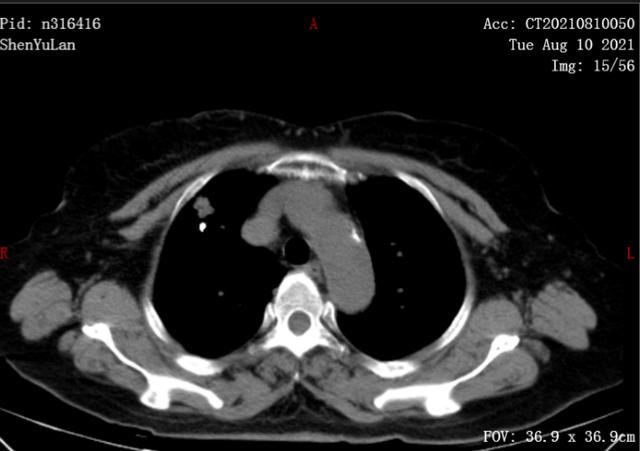

ct显示左肺上叶有支气管内肿块,伴有远端黏液嵌塞,主动脉旁和左支气管